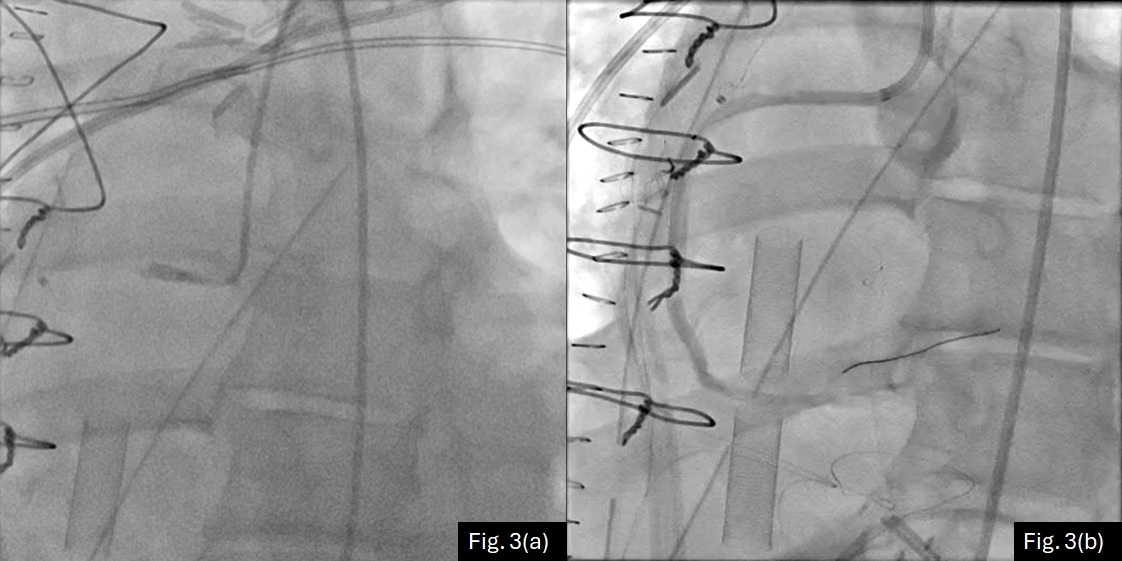

The patient was brought to the OR for mediastinal debridement and removal of the LV vent for the purpose of assessing ventricular function and improving arterial pulsatility. Pulse pressure remained negligible at an ECMO flow of 4.5 L/min. Transeosphageal echocardiography (TEE) demonstrated extensive thrombosis of the aortic root, particularly involving the right and non-coronary sinuses (Fig 1a). The aortic valve (AV) did not open. Patency of the left main coronary ostium was evident by color Doppler (Fig 1b) although no right coronary artery (RCA) flow could be visualized. The tip of LV vent was seen tenting the anterior leaflet of mitral valve (MV) causing significant regurgitation. (Fig. 2a-d)